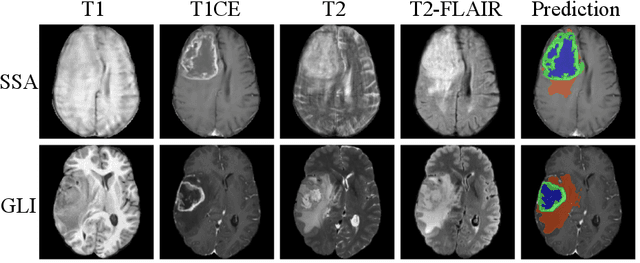

Abstract:Gliomas, a kind of brain tumor characterized by high mortality, present substantial diagnostic challenges in low- and middle-income countries, particularly in Sub-Saharan Africa. This paper introduces a novel approach to glioma segmentation using transfer learning to address challenges in resource-limited regions with minimal and low-quality MRI data. We leverage pre-trained deep learning models, nnU-Net and MedNeXt, and apply a stratified fine-tuning strategy using the BraTS2023-Adult-Glioma and BraTS-Africa datasets. Our method exploits radiomic analysis to create stratified training folds, model training on a large brain tumor dataset, and transfer learning to the Sub-Saharan context. A weighted model ensembling strategy and adaptive post-processing are employed to enhance segmentation accuracy. The evaluation of our proposed method on unseen validation cases on the BraTS-Africa 2024 task resulted in lesion-wise mean Dice scores of 0.870, 0.865, and 0.926, for enhancing tumor, tumor core, and whole tumor regions and was ranked first for the challenge. Our approach highlights the ability of integrated machine-learning techniques to bridge the gap between the medical imaging capabilities of resource-limited countries and established developed regions. By tailoring our methods to a target population's specific needs and constraints, we aim to enhance diagnostic capabilities in isolated environments. Our findings underscore the importance of approaches like local data integration and stratification refinement to address healthcare disparities, ensure practical applicability, and enhance impact.